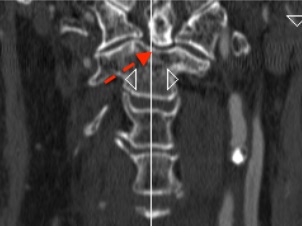

La reconstrucción sagital puede inducir a error al creer que la fractura (flecha verde) puede tratarse de manera conservadora ( tipo I)

Sin embargo, la reconstrucción coronal del mismo paciente nos indica claramente que la fractura (flecha roja) se ubica en la base de la odontoides